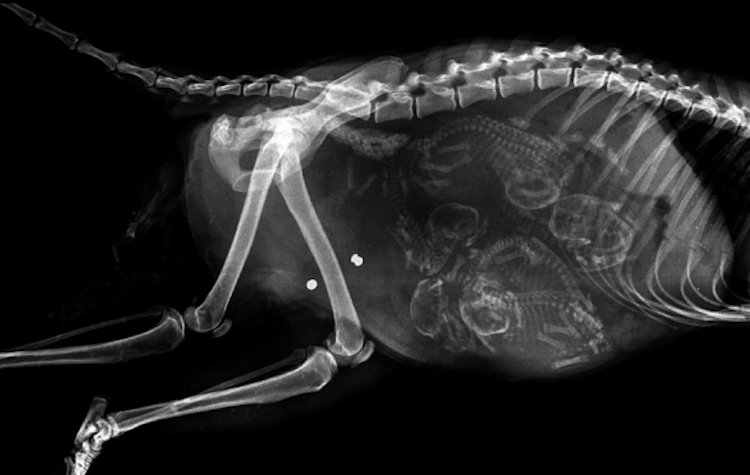

3 – Chatte enceinte. Les chattes peuvent tomber enceinte à 4 mois. À environ 45 jours de grossesse, les squelettes des chatons sont assez formés pour être visibles aux rayons X.